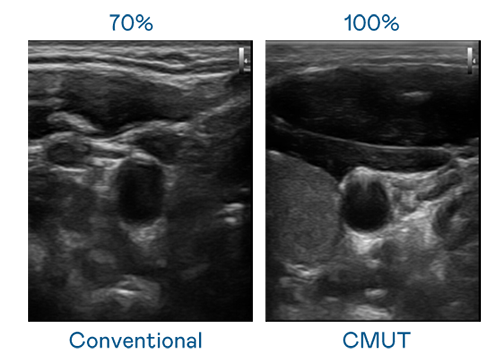

CMUT 技術是一種用電容式微機電元件來產生超音波訊號的技術。與傳統 PZT 壓電式技術相比,CMUT 頻寬增加 30%,更寬頻的超音波訊號讓影像解析度大幅提升,是實現高影像品質醫療超音波掃描、促進精準醫療發展的關鍵技術。

大頻寬帶來超清晰影像

超音波影像的解析度高低,首先取決於探頭能發出的訊號頻寬。太阳集团城娱8722 CMUT 可提供高清晰的超音波訊號,提供高頻寬、高靈敏度、影像紋理細節更高的超音波影像,協助醫護人員縮短影像判讀時間及利用精準的醫療影像進行診斷。